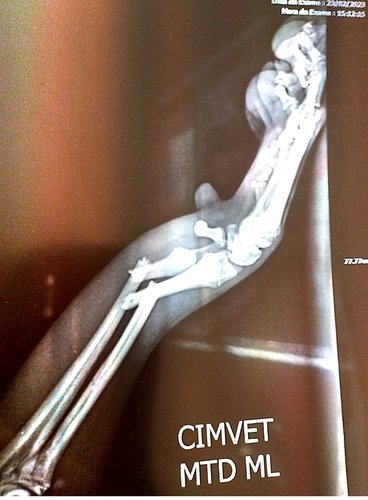

Oi meu nome é Valdirene e sou a mamãe do Billy, meu cachorrinho de estimação que ganhei de presente e me apaixonei por ele. Recentemente ele caiu de cima de uma cama e fraturou dois ossinhos de uma das patas e necessita fazer uma cirurgia e já se passou 15 dias e não consegui o dinheiro necessário para a cirurgia. Conto com a sua ajuda para realizar a cirurgia. Para mais informações entre em contato comigo 31 973660934.